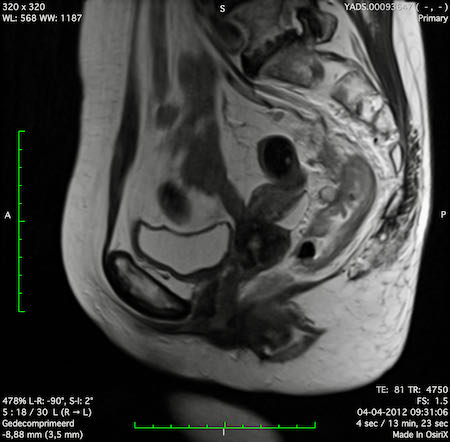

Hình ảnh

Các hình ảnh được cung cấp cho thấy ung thư biểu mô tế bào nhẫn với tình trạng dày lan tỏa thành trực tràng, hình ảnh bia bắn điển hình, và sự xâm lấn mỡ mạc treo trực tràng.